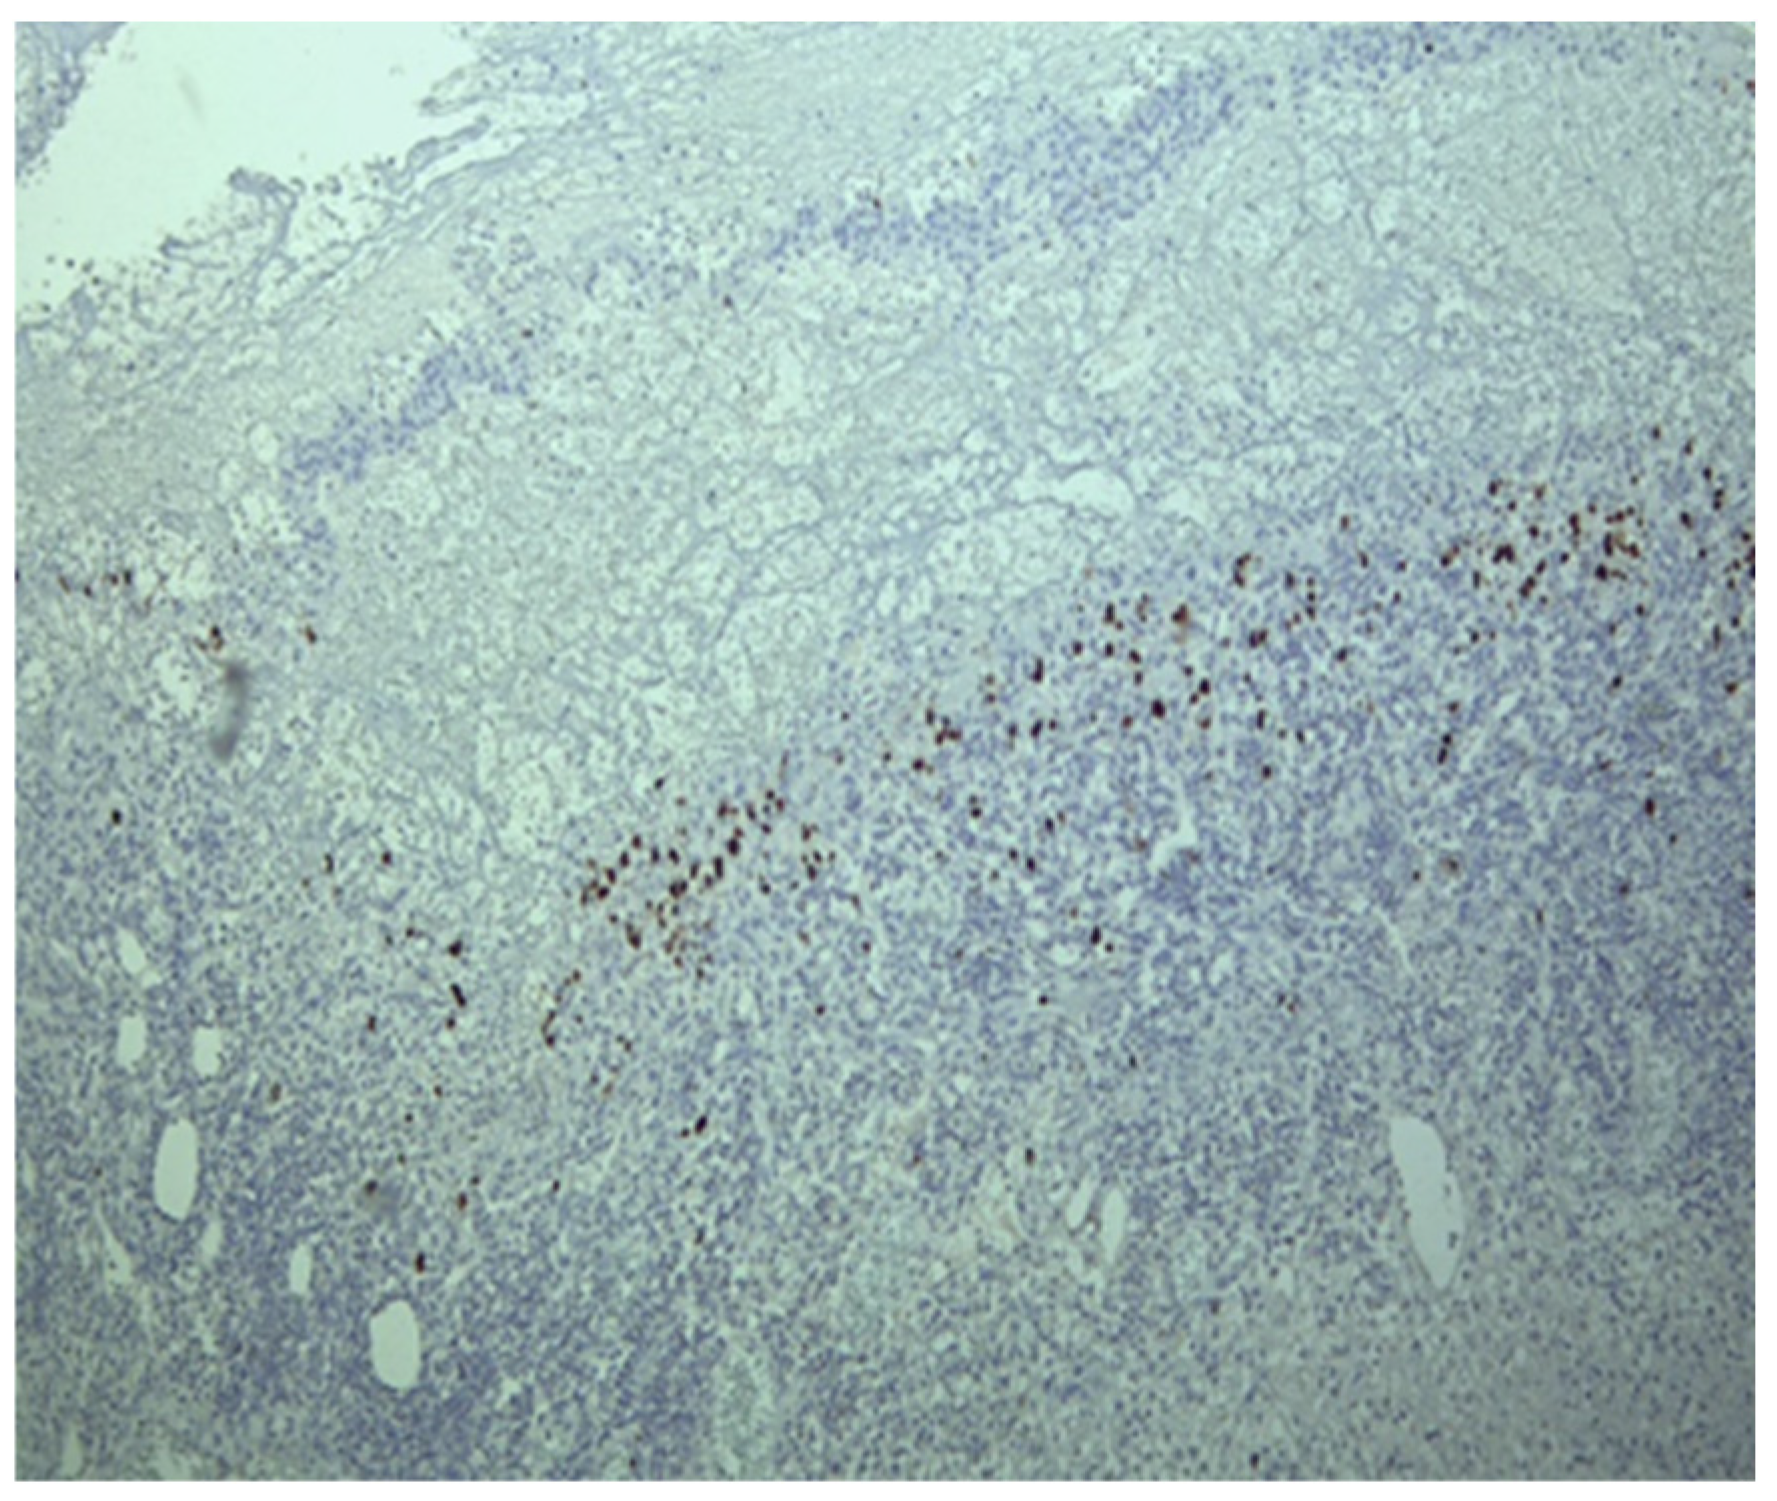

Figure 2.

Fragment of colonic mucosa with marked architectural distortion associated with abundant chronic inflammatory infiltrate, including basal plasmacytosis and areas of ulceration (Hematoxylin eosin staining, ×4).

Figure 3.

In the area of ulceration, numerous viral inclusions were detected by immunostaining.

Histological examination revealed crypt architectural distortion, associated with extensive chronic inflammation, including basal plasmacytosis, and active inflammation in the form of cryptitis and crypt abscesses, thus confirming the clinical diagnosis of ulcerative colitis. Treatment was initiated with corticosteroids, 5-ASA, and supportive therapy. Due to partial symptomatic improvement, the patient was discharged with treatment recommendations and follow-up instructions. One month later, she was readmitted due to the recurrence of symptoms. Ileocolonoscopy revealed persistent pancolitis with severe endoscopic activity characterized by longitudinal and deep ulcers (Mayo score of 10 points), as shown in Figure 1. Nine serial biopsies were taken: two from the ascending colon, two from the transverse colon, and five from the left colon, including from the bottom of the ulcers. Microscopically, the same pattern of chronic inflammation and associated ulcerations was observed. Notably, within the endothelial cells of the granulation tissue from the ulcerations, a high number of viral inclusions were identified, which tested positive on specific immunostaining for HCMV (Figure 2 and Figure 3).